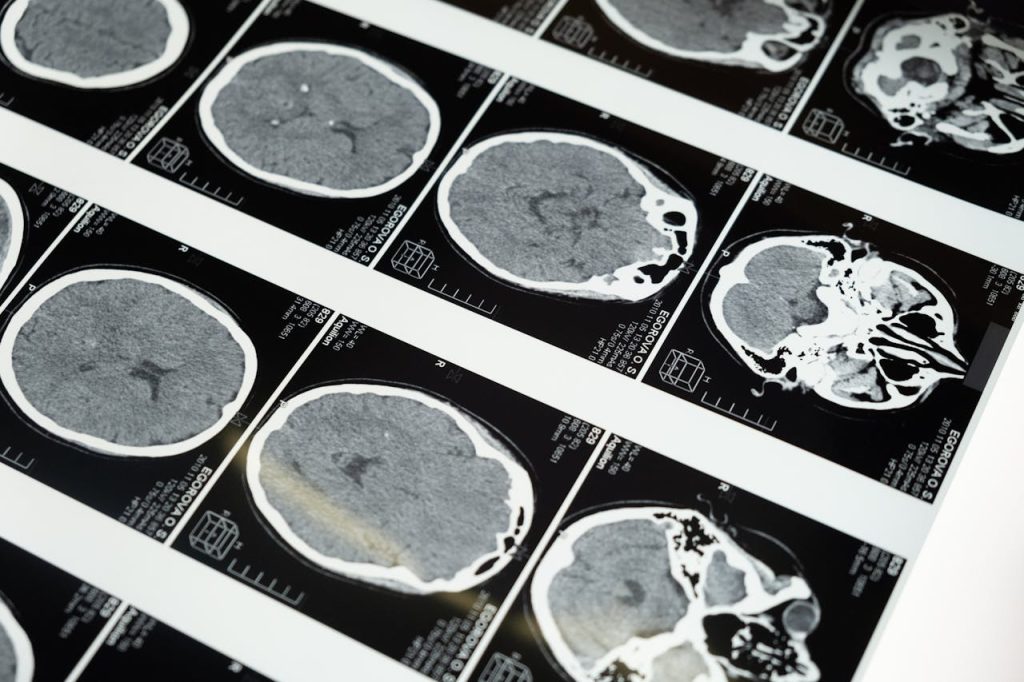

Nevrovitenskapelige funn

Moderne bildediagnostikk har gitt innsikt i hvordan hypnose påvirker hjernen. En studie publisert i Cerebral Cortex viser at hypnose kan modulere aktivitet i hjernens smertebaner, noe som forklarer dens smertelindrende effekter. Videre har forskning vist at hypnose kan påvirke aktiviteten i prefrontale korteks og amygdala, som er sentrale områder for oppmerksomhet, følelser og beslutningstaking. Dette kan forklare hvorfor hypnose er effektiv i behandling av stress, angst og depresjon. En annen viktig oppdagelse er at personer med høy hypnotiserbarhet har spesifikke nevrologiske mønstre som gjør dem mer mottakelige for hypnose, noe som åpner for muligheten for mer skreddersydde behandlingsformer. (Oxford Academic)